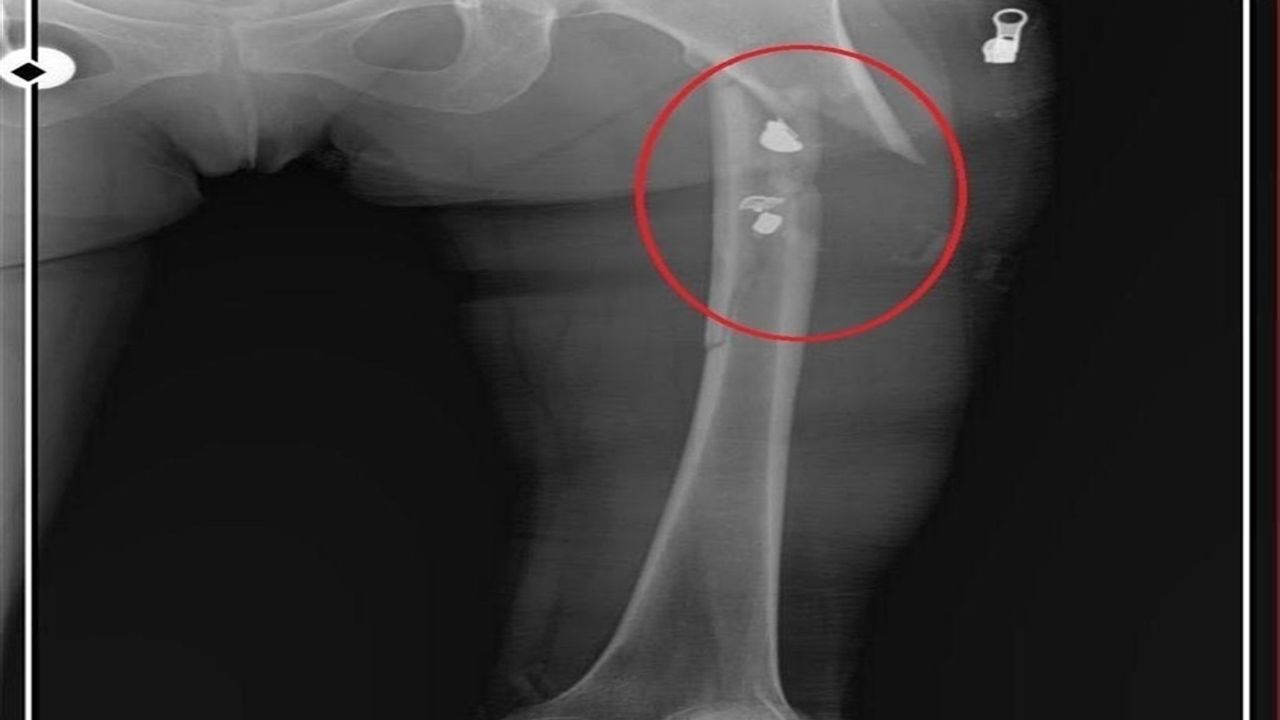

İlyas Sarıkaya, sevgilisi Fatma O.'yu da 8 kurşunla vurup, yaraladı. Arkadaşı Özaslan'ın cesedini önce çarşafa sonra da streç filme sarıp bantlayan Sarıkaya, eczaneden aldığı sargı bezi ve ilaçlarla pansumanını yaptığı sevgilisine yaralı haldeyken 21 gün boyunca cinsel saldırıda bulundu.